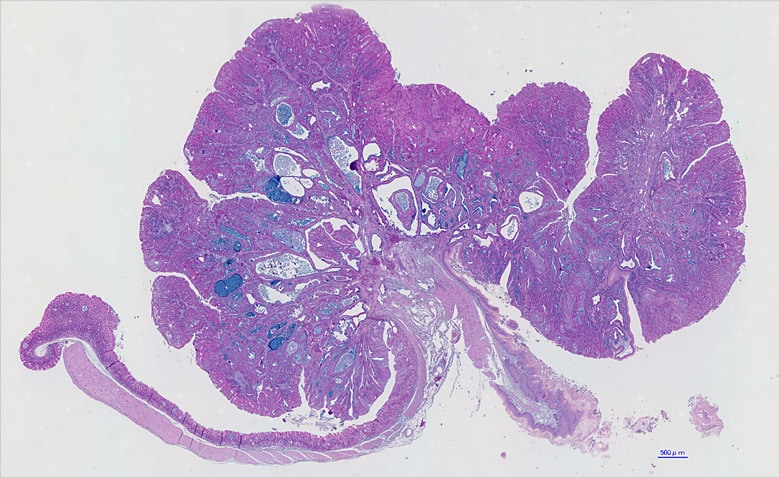

07. Klare Bilder durch Unschärfereduktion

Auch Wissenschaftler Dr. Takatsugu Ishimoto verwendet häufig die Modellreihe BZ im Labor von Dr. Saya. Gegenwärtig erforscht er die Entwicklung von Magenkrebs. Kürzlich wurde die Beteiligung von Helicobacter pylori als Ursache von Magenkrebs identifiziert, aber sein Mechanismus im lebenden Organismus ist noch nicht vollständig erforscht. Durch die Forschung an transgenen Mäusen versucht Dr. Ishimoto, auf molekularer Ebene den Mechanismus zur Entstehung von Magenkrebs zu entschlüsseln.

Dr. Ishimoto verwendet die Modellreihe BZ zur Beobachtung des gesamten Mäusemagens und ebenso Teilabschnitte davon.

„Am beeindruckendsten sind die klaren Bilder. Ich finde die Unschärfereduktionsfunktion, welche die Fluoreszenzunschärfe beseitigt, sehr praktisch. Sie kann die Entwicklung der Probenzellen deutlich sichtbar machen und liefert überzeugende Bilder.“